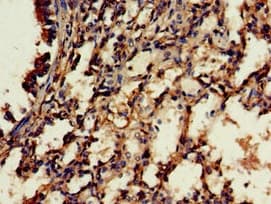

Rabbit Polyclonal C18orf22/RBFA antibody. Suitable for WB, IHC-P and reacts with Human, Mouse, Rat samples. Cited in 1 publication. Immunogen corresponding to Recombinant Fragment Protein within Human RBFA aa 200 to C-terminus.

Applications IHC-P, WB